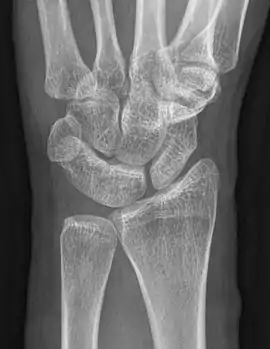

An example of a coalition between the trapezoid and capitate carpal bones

The lunate and triquetral bones are the most common carpal bones to fuse together, resulting in a lunotriquetral coalition in 1% of people. 60% of patients with a lunotriquetral coalition will have it bilaterally.[1] Among isolated incidents the capitate and hamate bones are the next most common to fuse followed by the pisiform-triquetrum, trapezium-trapezoid, scaphoid-capitate, and triquetrum-hamate.[3]

Carpal coalitions may further be divided into four subtypes:[3]

• Type 1 - incomplete fusion with pseudoarthrosis

• Type 2 - fusion with a "notch" between the fused bones

• Type 3 - complete fusion

• Type 4 - complete fusion with other anomalies present